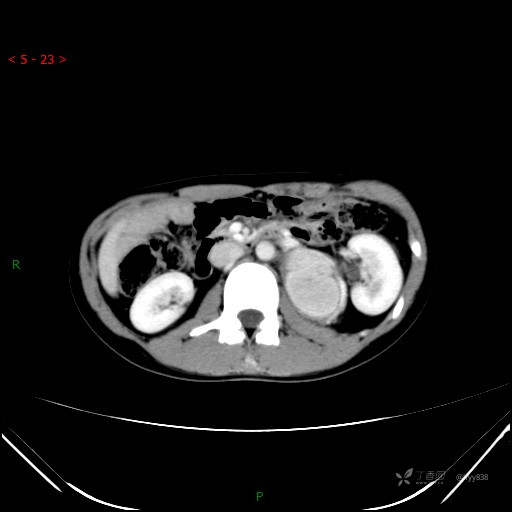

腹部CT平扫

增强动脉期